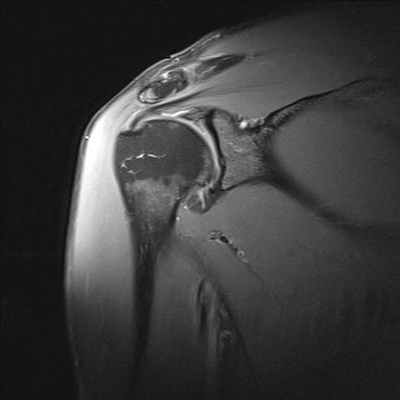

МРТ плечевого сустава

Плечелопаточный периартрит (периартроз, периартикулярные поражения области плечевого сустава) - собирательный термин всех периартикулярных поражений области плечевого сустава. Нередко боли в области плечевого сустава вызваны не поражением самого сустава, а околосуставных мягких тканей. Наиболее частой причиной острой или хронической боли в области плечевого сустава является дегенеративно-воспалительное поражение сухожилий мышц, участвующих в движениях плеча (тендиниты). От чрезмерной физической нагрузки (у маляров, спортсменов и людей других профессий) сухожильные волокна растягиваются и надрываются. В конечном итоге развивается воспалительный процесс. Острый период с резкими болевыми ощущениями у таких пациентов длится обычно несколько недель, и при эффективном лечении интенсивность болей в плече снижается, функция сустава восстанавливается. Однако благоприятное течение заболевания с полным выздоровлением заканчивается далеко не у всех. У многих больных при неблагоприятном развитии патологического процесса боли в плече не проходят, а подчас усиливаются не только при физической нагрузке, но и в покое, приобретают постоянный характер. Движения в суставе, как правило, сопровождаются хрустом различной интенсивности. В далеко зашедших случаях может возникнуть тугоподвижность сустава, атрофия мышц и остеопороз головки плечевой кости. При рентгеновском исследовании чаще всего определяется кальцификация (отложение солей) в суставных сумках и в окружающих сустав тканях. МРТ дает полную картину патологических изменений в периартикулярных тканях на ранних этапах заболевания - это отек в области сухожилий, их истончение или неполный разрыв, наличие выпота в суставных синовиальных сумках, атрофия отдельных групп мышц и др. Среди основных показаний к МРТ исследованию плечевого сустава являются нестабильности в суставе и разрывы вращательной манжеты плеча.

Нестабильность плечевого сустава отмечается при слабой фиксации головки плечевой кости в суставной впадине лопатки, которая приводит к повышенной подвижности в суставе и часто к развитию вывихов и подвывихов при травмах, определенных положениях руки (например, при бросании предметов из-за головы вперед). Если диагностика вывихов не представляет особых затруднений при обычном рентгенологическом исследовании, то подвывихи не всегда четко визуализируются при данном методе лучевой диагностики. МРТ диагностика в этих случаях позволяет визуализировать даже незначительные нарушения взаимоотношений головки плечевой кости и суставной впадины лопатки.

Разрывы вращательной манжеты плеча являются наиболее частой причиной болевого синдрома в плечевом суставе во всех возрастных группах взрослого населения и невозможности поднять или отвести руку. МРТ диагностика при данной травме позволяет визуализировать как полный разрыв связок, так и частичное их повреждение. Как правило, сопутствующими осложнениями повреждений вращательной манжеты плеча является скопление жидкости в субакромиальной и поддельтовидной сумках (находятся между мышцами), что также хорошо выявляется при МРТ исследовании. А восстановление разрыва сухожилий вращательной манжеты является сложной хирургической операцией.

МРТ признаки повреждения акромиально-ключичного сочленения на уровне плечевого сустава